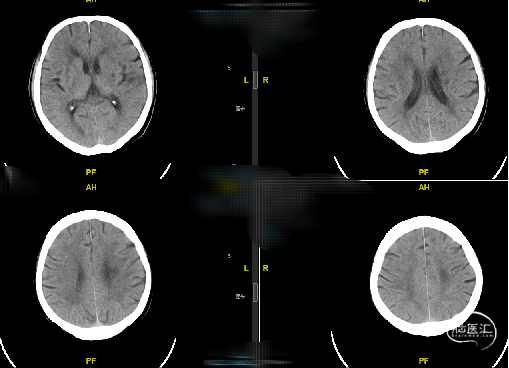

现病史:患者一月余前出现右侧肢体麻木无力,为发作性,持物行走欠稳,无视物模糊、视物旋转,无耳鸣、听力下降,无肢体抽搐强直,13天前于我院神经内科住院治疗,患者右侧肢体无力好转,病程中查彩超及头颈部CTA提示双侧椎动脉开口重度狭窄。

辅助检查(CTA):双侧椎动脉开口重度狭窄,左侧椎动脉为优势动脉,椎动脉颅内段及基底动脉显影良好。

随访:患者术后一般情况好,神经系统查体无明显异常,复查头颅CT未见新发梗死/出血,血压控制良好,好转出。

现病史:患者3年前因“脑梗死”于我院神经内科住院期间行颈部血管彩超检查提示左侧椎动脉中重度狭窄,未予重视,2年前复查血管彩超提示左侧椎动脉开口重度狭窄,予药物治疗,9月前复查头颈部CTA提示双侧椎动脉开口重度狭窄,6天前复查颈部血管彩超亦提示双侧椎动脉开口处重度狭窄。

辅助检查(CTA):双侧椎动脉开口重度狭窄。

随访:患者术后一般情况好,神经系统查体无明显异常,血压控制良好,术后第二天复查头颅CT未见出血/梗死并发症。